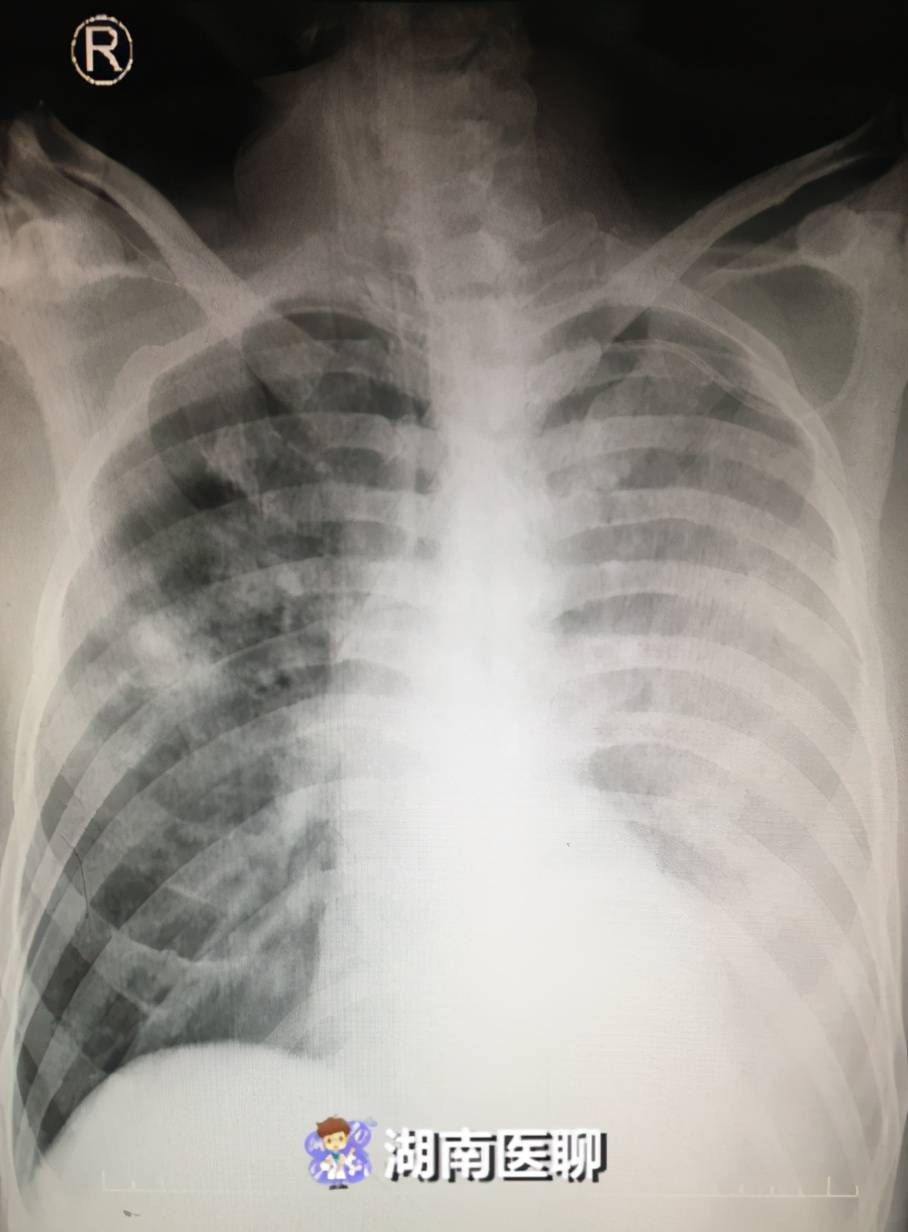

教科书上也很少见这么经典的胸片附肺实变的轮廓征图

(患者入院胸片)但在短短3天时间内,患者病情进行性加重,迅速恶化,来势

看到空气支气管征,要想到这些 胸片中通常观察不到支气管,当肺实质